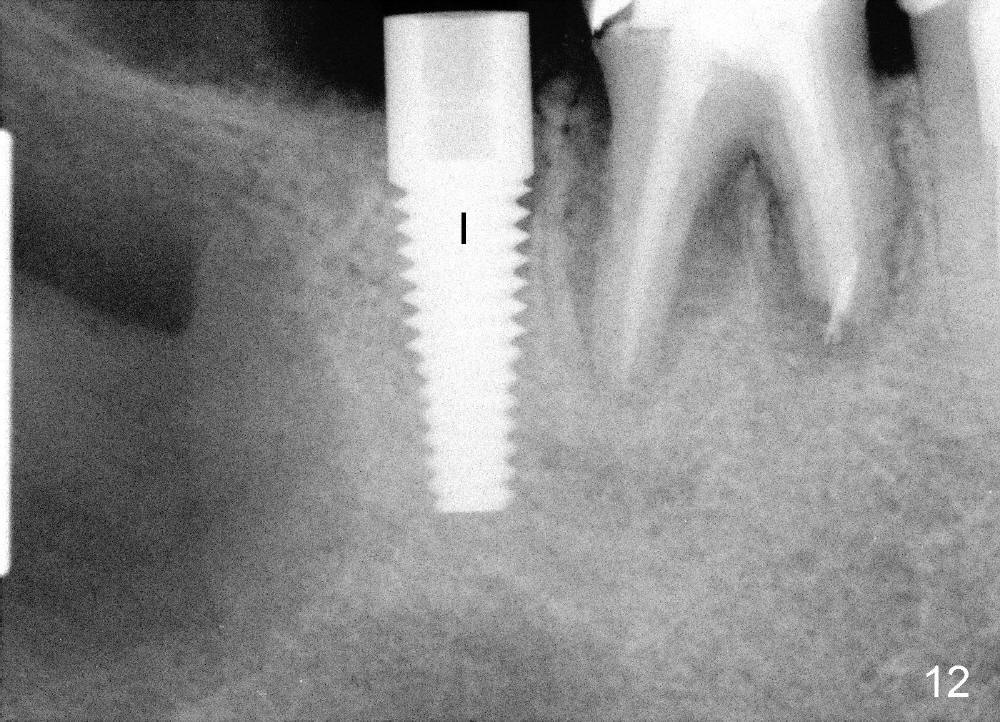

Then the

cyst is removed; hemorrhage is being controlled by gauze (Fig.10 *), while the

osteotomy is created in the mesial socket of #31 (4.5x17 mm tap in place: T

(Fig.10,11)). A 5x17 mm implant is placed with high torque (Fig.12 I).